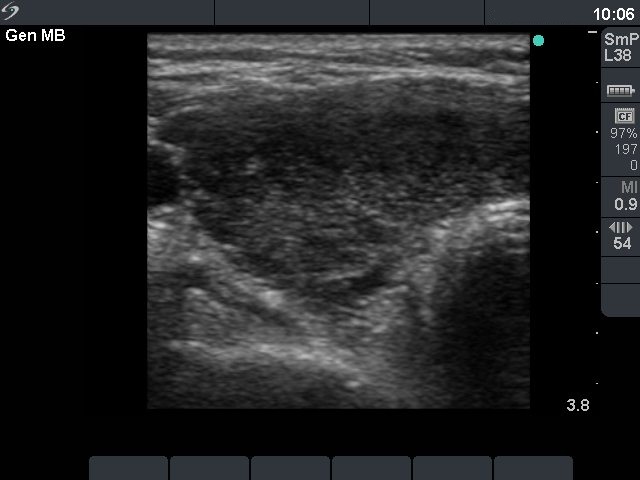

First examination (first row of ultrasound images)

Clinical data: a 37-year-old woman was referred for an evaluation of typical complaints suggesting hyperthyroidism and signs of mild thyroid associated orbitopathy.

Palpation: both thyroids were enlarged.

Functional state: hyperthyroidism (TSH undetectable, FT4 above 75 pM/L).

Ultrasonography: the thyroid was diffusely hypoechogenic without any nodule. The vascularization was increased.Thyrostatic drug was administered and the patient went on regular follow-up examinations.